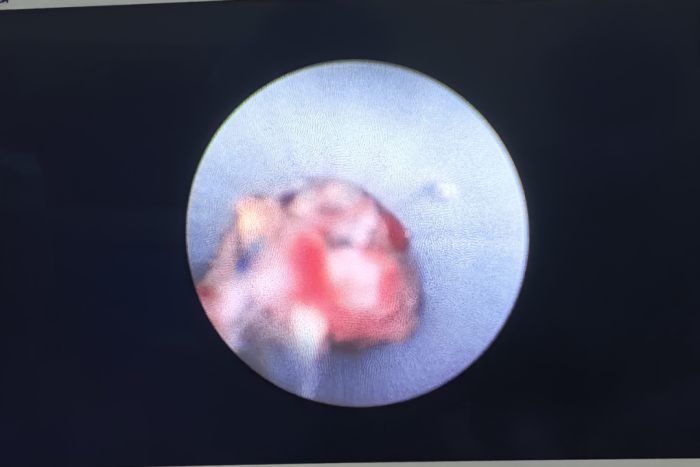

经朋友介绍,徐先生来到桂林医科大学第二附属医院,肝胆胰外科团队为其实施经腹壁窦道肾镜清创术,术中彻底清创腹腔内坏死感染组织并留置伤口引流管,术后第2天携带引流管出院。留置的引流管引出少量渗液,一周后复查CT腹腔内感染灶逐步愈合,最终拔除引流管,彻底治愈。目前徐先生已安然无恙,开启了新的生活和工作。

近几年,科室核心成员吴嘉兴副教授通过超声或CT引导腹腔或腹膜后穿刺置管引流治愈了大量腹腔感染患者,对于腹壁有窦道的患者可选择硬镜直视下清创,此方法具有安全、高效的特点,不仅可避免再次开腹手术,而且更加微创,患者获益更大。